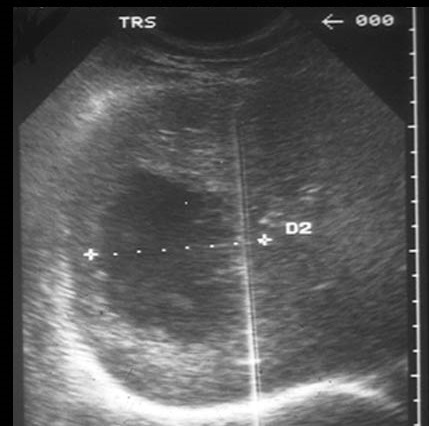

Image echographique de abces

du foie lobe droit . Aspect arrondie uniloculaire hyperechogen

avec region aechogen central sa paroi est

epaise , hyperechogene .image echographique peut

oriente vers une abces amibien |